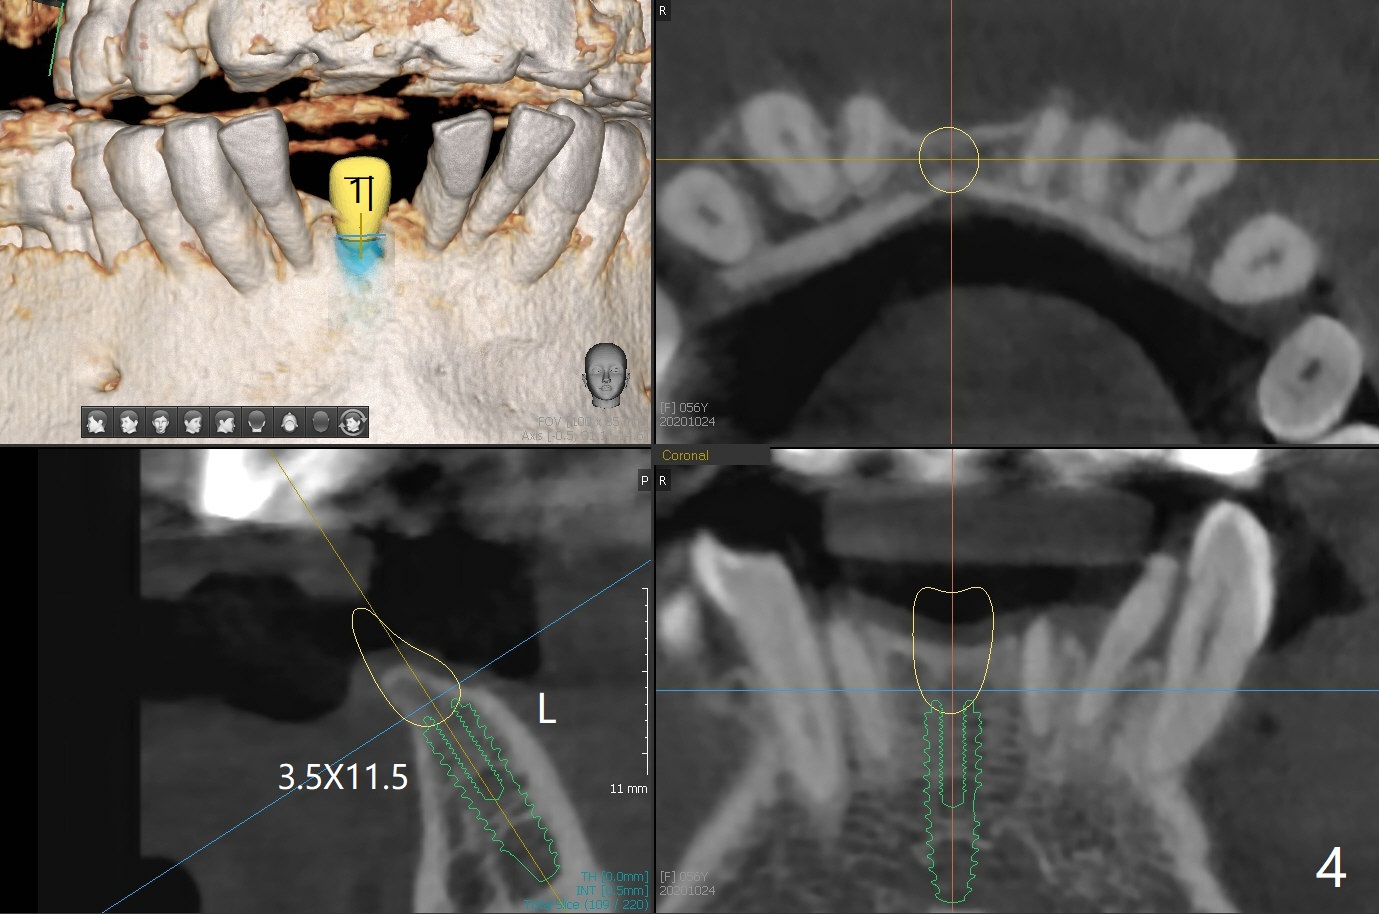

56岁女牙周炎,失去右上6,7以及右下1,后者缺牙间隙特别宽,其余切牙往颊侧移位(flare,病人不愿意拔除,图一)。右上植牙修复后(图二,三),下前牙种植(图四,五(选择窄植体)),建立正常覆盖,同时在邻近切牙唇侧植骨(图七,八:红线)。四-六个月后做局部矫正:使用植牙作为支抗将颊侧移位的前牙(牙冠)往舌侧推移(图七,八:蓝箭头),而牙根可能往唇侧移位(图六:红箭头),所以事先植骨(图七,八:红线)重要。矫正后3-3舌侧放置钢丝树脂固定。Jennifer: #25 implant and crown should be lingualized, as compared to the rest of the lower incisors (flared). After osteointegration, ortho will be conducted to correct the flaring using #25 implant as an anchor.